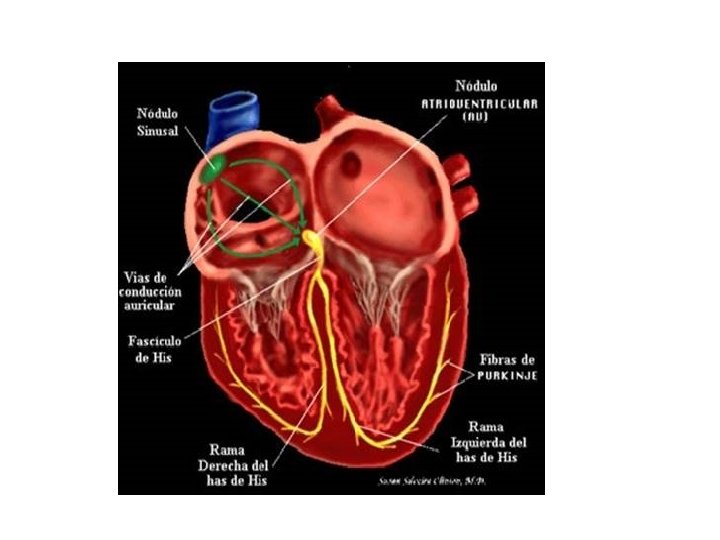

• Más abajo yace una capa de tejido conectivo denso que contiene abundantes fibras elásticas entremezcladas con células de musculo liso. En lo profundo, al endocardio se encuentra una capa subendocardica de tejido conectivo laxo que contiene vasos sanguíneos pequeños, nervios y fibras de Purkinje del sistema de conducción del corazón.

MIOCARDIO • La capa media y más gruesa de las tres capas del corazón • Contiene células de músculo cardiaco dispuestas en espirales alrededor de los orificios de las cámaras. • Algunas células de músculo cardiaco fijan el miocardio al esqueleto cardiaco fibroso. Otras están especializadas en secreciones endocrinas y unas más acondicionadas para generar impulsos o conducirlos.